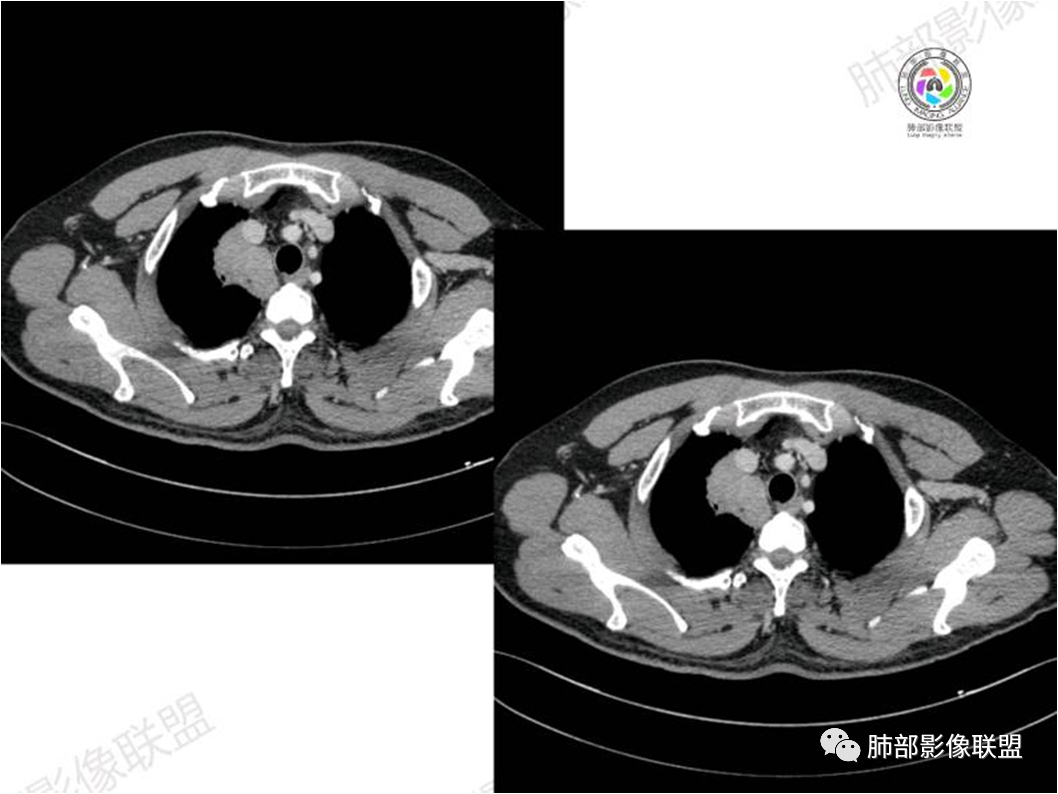

黏膜相关淋巴组织(Mucosa associated lymphoid tissue, MALT)淋巴瘤是来源于黏膜相关淋巴 组织边缘带的低度恶性非霍奇金B细胞淋巴瘤。肺MALT淋巴瘤较为罕见,约占淋巴瘤的0.14%~1%,易被误诊为肺炎或肺癌。

MALT淋巴瘤这一概念最早由Isaacson和 Wright等于1983年提出,其可发生全身具有黏膜的器官或组织,最常见于胃肠道,其次为肺(15%)组织,病因不明,目前多认为与慢性感染、吸烟或自身免疫性疾病有关。肺MALT淋巴瘤是较为罕见的低度恶性肿瘤,多见于50-70岁,男女发病率无明显差异,或男性略多于女性。

⑥肺门及纵隔淋巴结肿大少见;

肺MALT淋巴瘤需要与大叶性肺炎、肺结核、肺癌及继发性淋巴瘤等鉴别。大叶性肺炎多有高热症状,CT多表现为单个肺叶实变影,很少跨叶分布,充气支气管管径及形态正常。肺结核多有低热、盗汗症状,多发生于两肺上叶尖段及下叶背 段,多可见长毛刺、钙化或空洞,周围常见卫星灶,结核菌素试验阳性。肺炎型肺癌临床症状常较轻,部分因含量黏液而密度偏低,充气支气管可呈扭曲不规则狭窄、中断。肺癌CT表现为肺部肿块,可有分叶、毛 刺征、空泡征、血管集束征及胸膜凹陷征,肿块可有支气管中断、闭塞,可伴有肺门及纵隔淋巴结肿大。继发性淋巴瘤有肺外淋巴瘤的表现,除肺内病变外,常有肺门及纵隔淋巴结肿大。